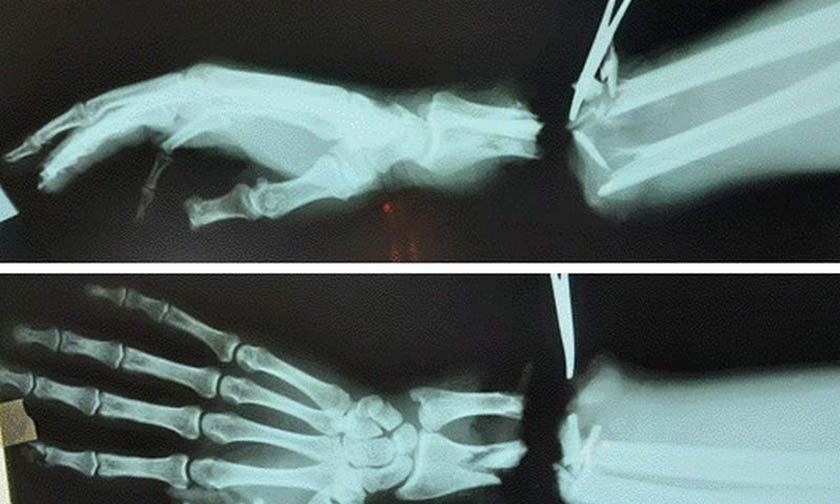

Курганские врачи пришили оторванную руку мужчине

Житель Шадринска получил тяжелую травму на производстве — ему оторвало кисть. Мужчину экстренно госпитализировали в районную больницу. Врачи приняли решение попытаться сохранить кисть, они оказали первую помощь и организовали доставку пациента в клинику реконструктивно-пластической хирургии и хирургии кисти Центра Илизарова.

Там была сделана сложная операция. Врачи сшивали сосуды, поврежденные нервы и кости, восстанавливали кровообращение. Операция длилась семь часов.

Фото: Центр Илизарова

Медики использовали шовный материал тоньше человеческого волоса, что потребовало особых навыков от хирурга.

«Результатом слаженной работы врачей клиники явилось полное приживление кисти с первичным восстановлением сухожильного аппарата, магистральных вен и артерий, а также невральных стволов, остеосинтезом поврежденных костных структур», — сообщили в клинике Илизарова.

Сейчас пациент проходит реабилитацию. Чтобы восстановить работу кисти, ему делают специальную «зарядку» для руки, электростимуляцию. У него уже активно сгибаются и разгибаются пальцы. В целом состояние пострадавшего врачи оценивают как нормальное.